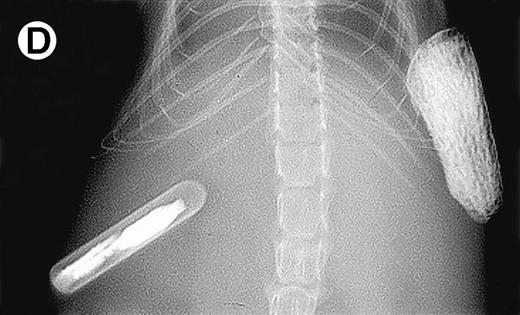

Growth of purified myeloma plasma cells (PC) from patient no. 1 in a SCID-hu host. SCID-hu host was inoculated with sorted PC. (A) Human Ig concentrations. (B) Dot plot of CD38/CD45 flow cytometry profile of the cells. The sort window used to purify plasma cells is shown. (C and D) X-radiograms showing severe resorption of the myelomatous implanted bone (C) compared with the nonmyelomatous bone of the control host (D), implanted at the same time as (C).